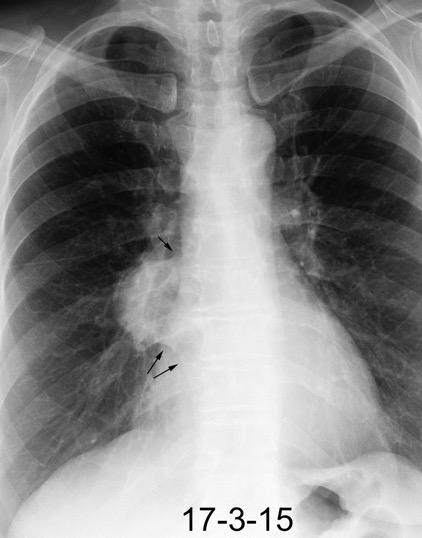

Triada de Garland

Ganglios paratraqueales derechos e hiliares bilaterales

95% de pacientes tienen ganglios hiliares bilaterales aislados o con afectación mediastínica (espec. paratraqueal derecho).

Criado E et al. Pulmonary sarcoidosis: typical and atypical manifestations at high-resolution CT with pathologic correlation. Radiographics. 2010